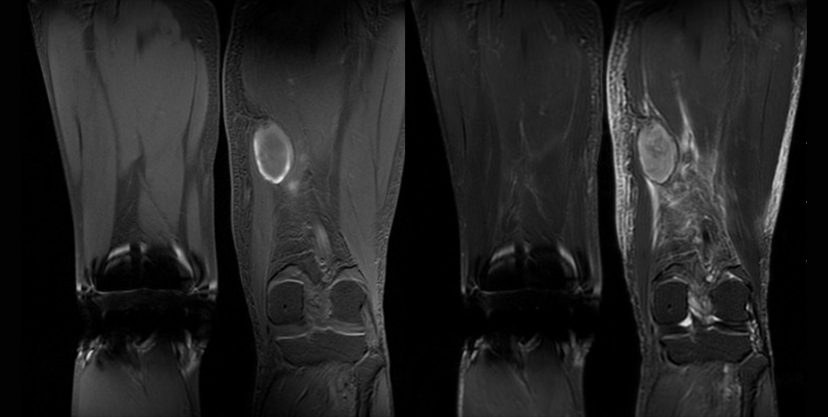

従来の3ポイントDIXONのIDEAL法の他に2ポイントDIXONのFlex法が使用可能となった。Flex法は、均一な脂肪抑制画像を取得でき、IDEALほど時間延長はなく非常に使い勝手の良いシーケンスである。手指や足趾などの磁場不均一が生じやすい部位に対しても、簡便に均一な脂肪抑制画像が取得でき大変重宝している。軟部腫瘍精査を目的とする際は、均一な脂肪抑制画像だけではなくIn phase画像が取得できるので、totalの検査時間が短縮され非常に有用である。